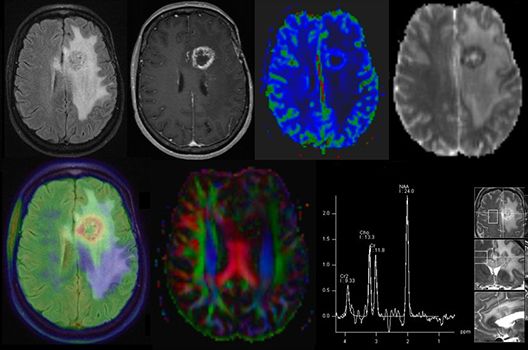

Die Hybridbildgebung mittels PET/MRT spielt insbesondere in der onkologischen Bildgebung eine wichtige Rolle. Eine mögliche Fragestellung ist die Unterscheidung zwischen einem Tumorrezidiv oder therapeutisch assoziierten Veränderungen insbesondere dann, wenn diese Frage mittels MRT alleine nicht beantwortet werden kann.

Die bildgebende Diagnostik und Verlaufsbeurteilung von Tumoren des Nervensystems ist einer der klinischen und Forschungsschwerpunkte unserer Abteilung. Eine besondere Bedeutung kommt der Hybrid-Bildgebung zu. Das Universitätsklinikum verfügt über einen integrierten Ganzkörper-PET/MRT-Scanner, der die Vorteile der MRT-Bildgebung und der Positronenemissionstherapie (PET) vereinigt. Aufgrund der langjährigen klinischen Arbeit und Forschungstätigkeit mit diesem Gerät hat die Neuroradiologie Tübingen maßgeblich zur Etablierung dieses Verfahrens beigetragen. Auch weiterhin forschen wir intensiv an neuen Methoden zur frühen Einordnung von Tumoren und insbesondere Tumorrezidiven, die mit anderen Methoden häufig nicht erfasst werden können.